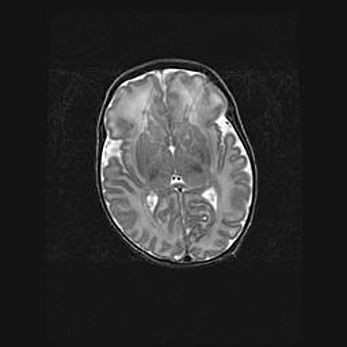

Множественные кисты обоих полушарий головного мозга, наибольшая из них в правой затылочной области. Ассиметричная атрофическая гидроцефалия.

Возраст: 7 месяцев

Вес: 5660 г

Пол: мужской

Окружность головы: 41,5 см

Срок гестации: 28-29 недель

Кисты головного мозга развиваются в результате многоочаговых некрозов вещества мозга и возникают вследствие перенесенной перинатальной инфекции, менингитов, энцефалитов, асфиксии, родовой травмы, расстройств мозгового кровообращения различного генеза. Образованию кист в веществе головного мозга плодов и новорожденных способствуют такие факторы, как высокое содержание в нем воды, недостаточная (или отсутствие) миелинизация и слабая астроглиальная реакция на повреждение.

Кисты могут сочетаться с гидроцефалией и другими поражениями головного мозга.